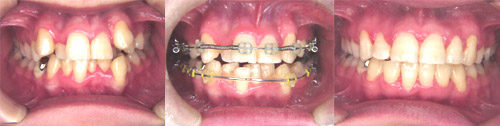

実際の治療  ( 実際に当クリニックで治療を終了された患者さんの写真を、許可を得て掲載しております。) 特別治療 【裏側矯正】 歯の裏側に矯正装置を装着して治していく治療法です。表側から装置が目立たないのが特徴です。

歯に矯正器具をつけ歯を動かして治療します。矯正器具は 金属のもの、セラミックの もの、裏側からつけるものがあります